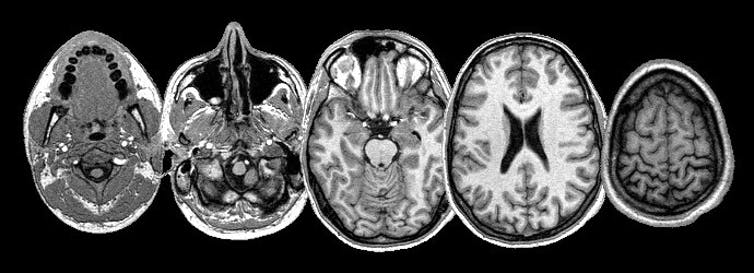

MRI images

Research based on MRI images usually exclude the skull. Wikimedia Commons., CC BY-SA